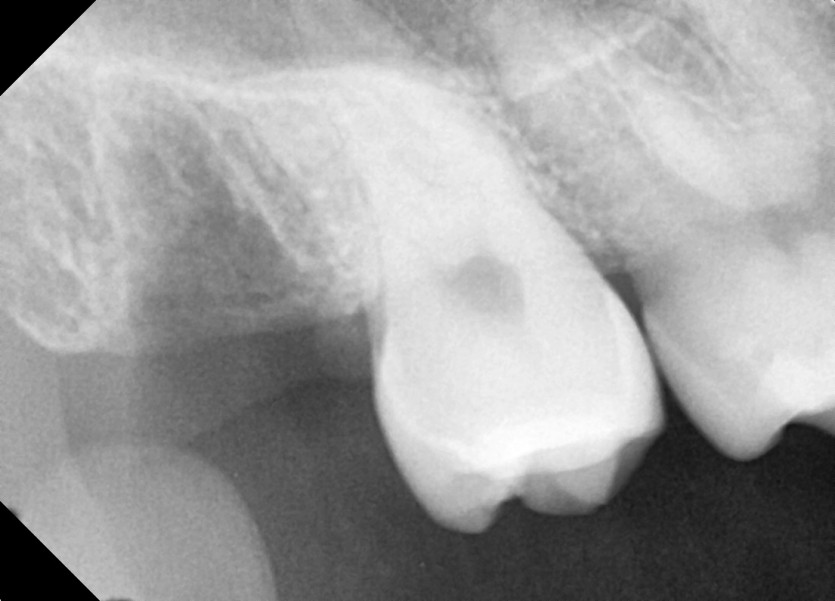

#18,48 사랑니 발치

구강외과 전문의가 당일발치했습니다.